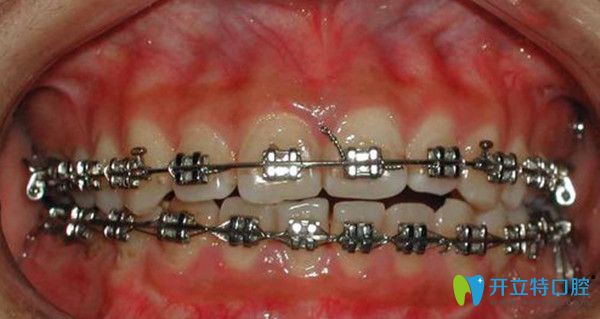

牙齒開(kāi)合常見(jiàn)于恒牙期,所謂的開(kāi)合指的是上下牙弓及頜骨垂直向的發(fā)育異常,在牙齒咬合時(shí),上下頜部分牙齒在垂直向無(wú)法接觸??赡苡梦淖謥?lái)敘述大家沒(méi)有一個(gè)直觀的了解,那么可以看下面這張照片:

牙齒開(kāi)合的照片

看完圖片,相信大家也更加直觀的了解到了什么是牙齒開(kāi)合,那么究竟是什么原因引發(fā)的牙齒開(kāi)合呢?